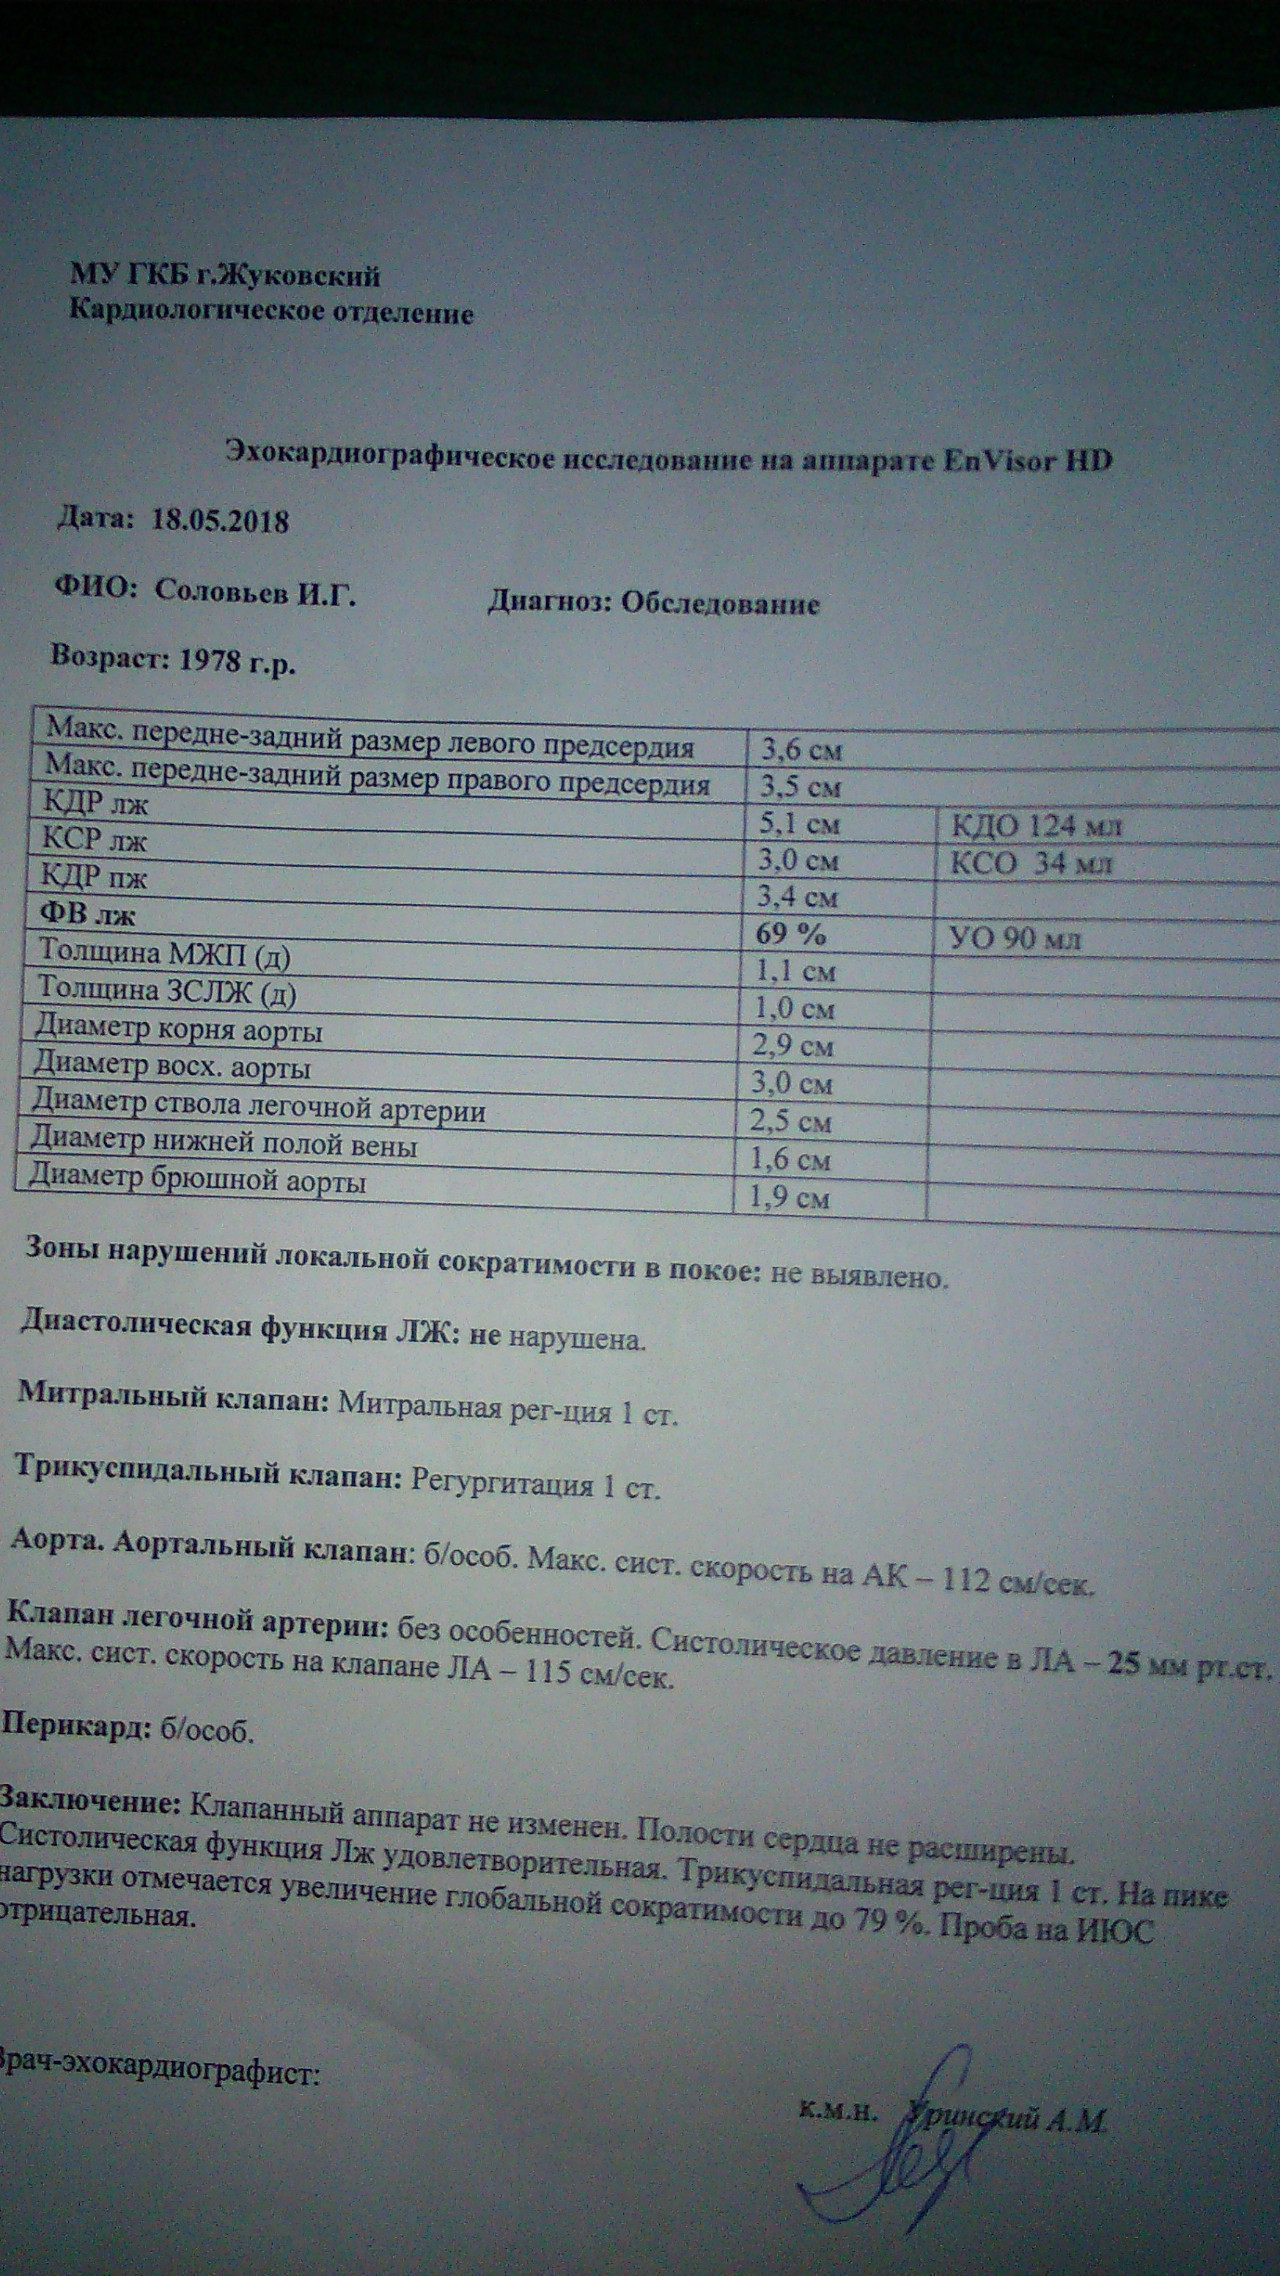

Нормальный диаметр корня аорты: медицинские нормы и отклонения